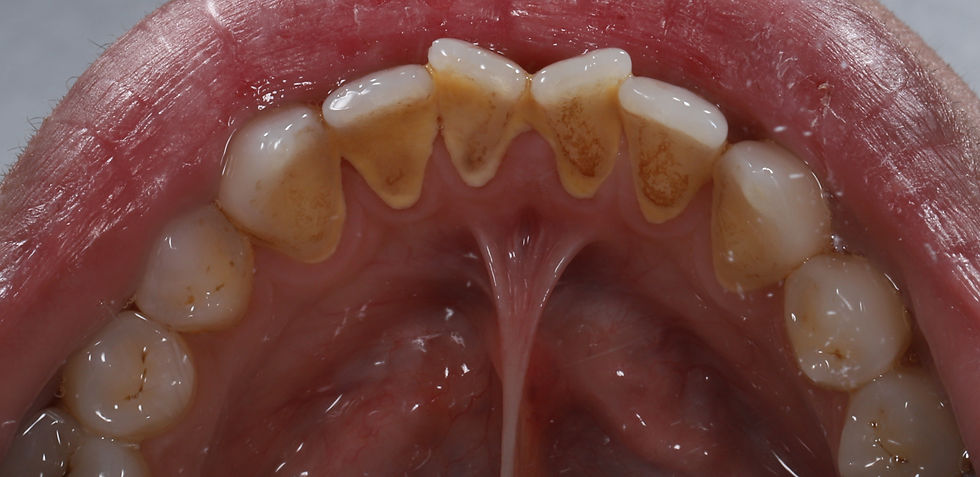

When teeth are crowded, overlapping, or rotated, they create narrow, irregular spaces that are difficult to reach with a toothbrush or floss. These areas become ideal environments for plaque to accumulate. Over time, plaque hardens into tartar a mineralised deposit that irritates the gums and contributes to inflammation.

Even individuals with excellent brushing technique can struggle with plaque removal in misaligned areas. Crowded teeth create traps where bacteria flourish and minerals from saliva harden the plaque into tartar.

By aligning the teeth, the surfaces become smoother and more accessible. This leads to a noticeable reduction in tartar accumulation after professional cleaning. Patients often report that their hygiene appointments become more comfortable, quicker, and feel cleaner for longer after achieving alignment.

Tartar management becomes significantly easier when teeth no longer overlap or hide difficult-to-clean surfaces.